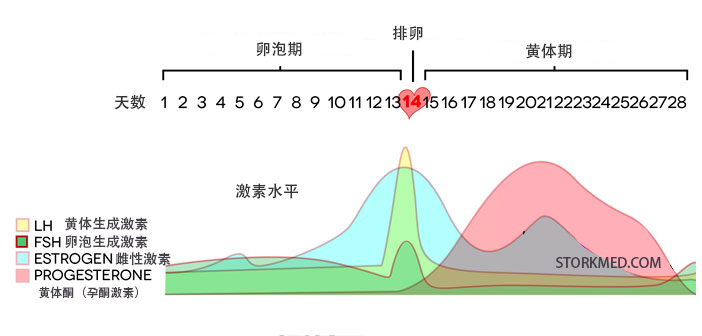

正常育龄期妇女的卵巢在下丘脑—垂体—卵巢轴(HPO轴)的作用控制下,每月都会发生规律月经和排卵。当一些疾病干扰HPO轴导致卵巢功能异常时,就会出现不排卵。不排卵的...

很多女性不孕的一个原因是黄体功能不足,黄体功能不足又称为黄体缺陷,下面介绍下什么是黄体期缺陷以及如何改善。黄体期缺陷有哪些症状?黄体酮水平低月经周期短或不规则大便...

黄体期:月经周期在排卵后,在下一次月经周期的第一天之前发生的部分称为黄体期,黄体期持续10至14天。一些有生育问题的女性的黄体期很短,复发性流产 、 连续两次或多...